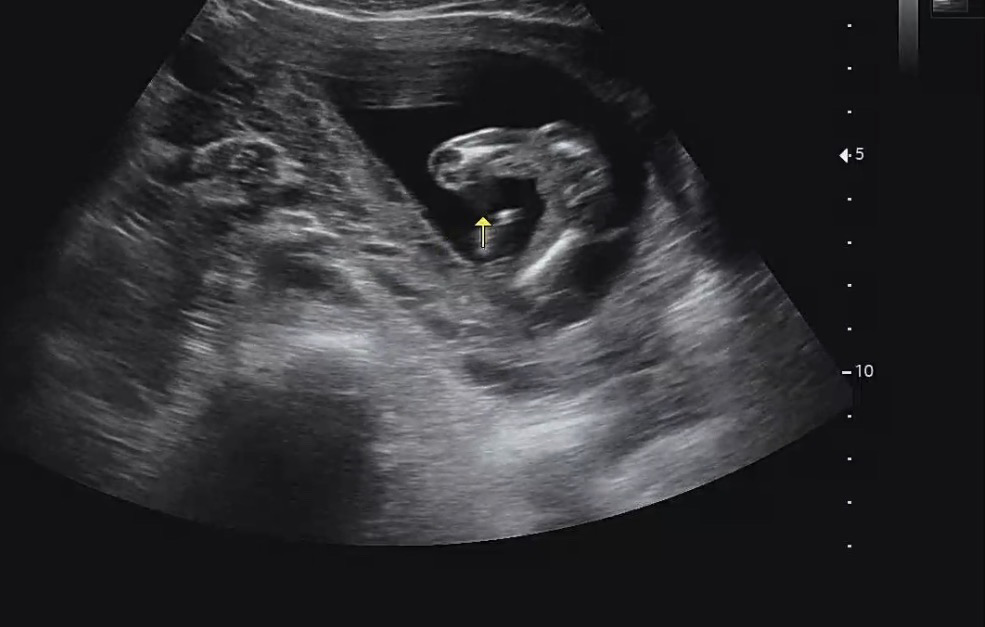

16주 초음파

16주 초음파 보고 왔는데 딸일까요 아들일까요 ㅠㅠ